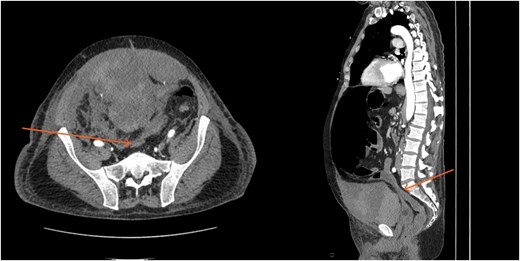

By hospital day 6, the patient’s condition improved. He was weaned from mechanical ventilation, his renal function improved (creatinine declined to 0.7 mg/dl), and hemoglobin stabilized at 8.4 gm/dl. The patient was clinically stable, and on hospital day 8, he was set up for discharge to a rehabilitation institution. However, on this day, he developed generalized abdominal pain associated with tachycardia, pulse = 118, and leukocytosis (white blood cells = 14.8 × 109/l). Physical exam revealed a distended abdomen with diffuse tenderness and sluggish intestinal sounds. A CT scan showed a large volume of pneumoperitoneum, minimal free fluid, and mildly dilated small bowel loops, consistent with a hollow viscus perforation with no identifiable source of perforation (Fig. 5) and a compression of rectosigmoid region against sacral promontory by the enlarged hematoma (Fig. 6). The right colon was decompressed compared with the prior study, and the RSH size remained unchanged, but there was progression of VTE burden. Prior to the acute deterioration, the patient had intermittently reported mild abdominal discomfort, which was initially attributed to the known RSH. There were no clinical signs suggestive of bowel obstruction, such as vomiting or significant abdominal distension. While the patient noted some degree of constipation, he reported that this was consistent with his baseline bowel habits and did not raise concern for new pathology.

CT scan demonstrating pneumo-peritoneum (arrow), indicative of a hollow viscus perforation.